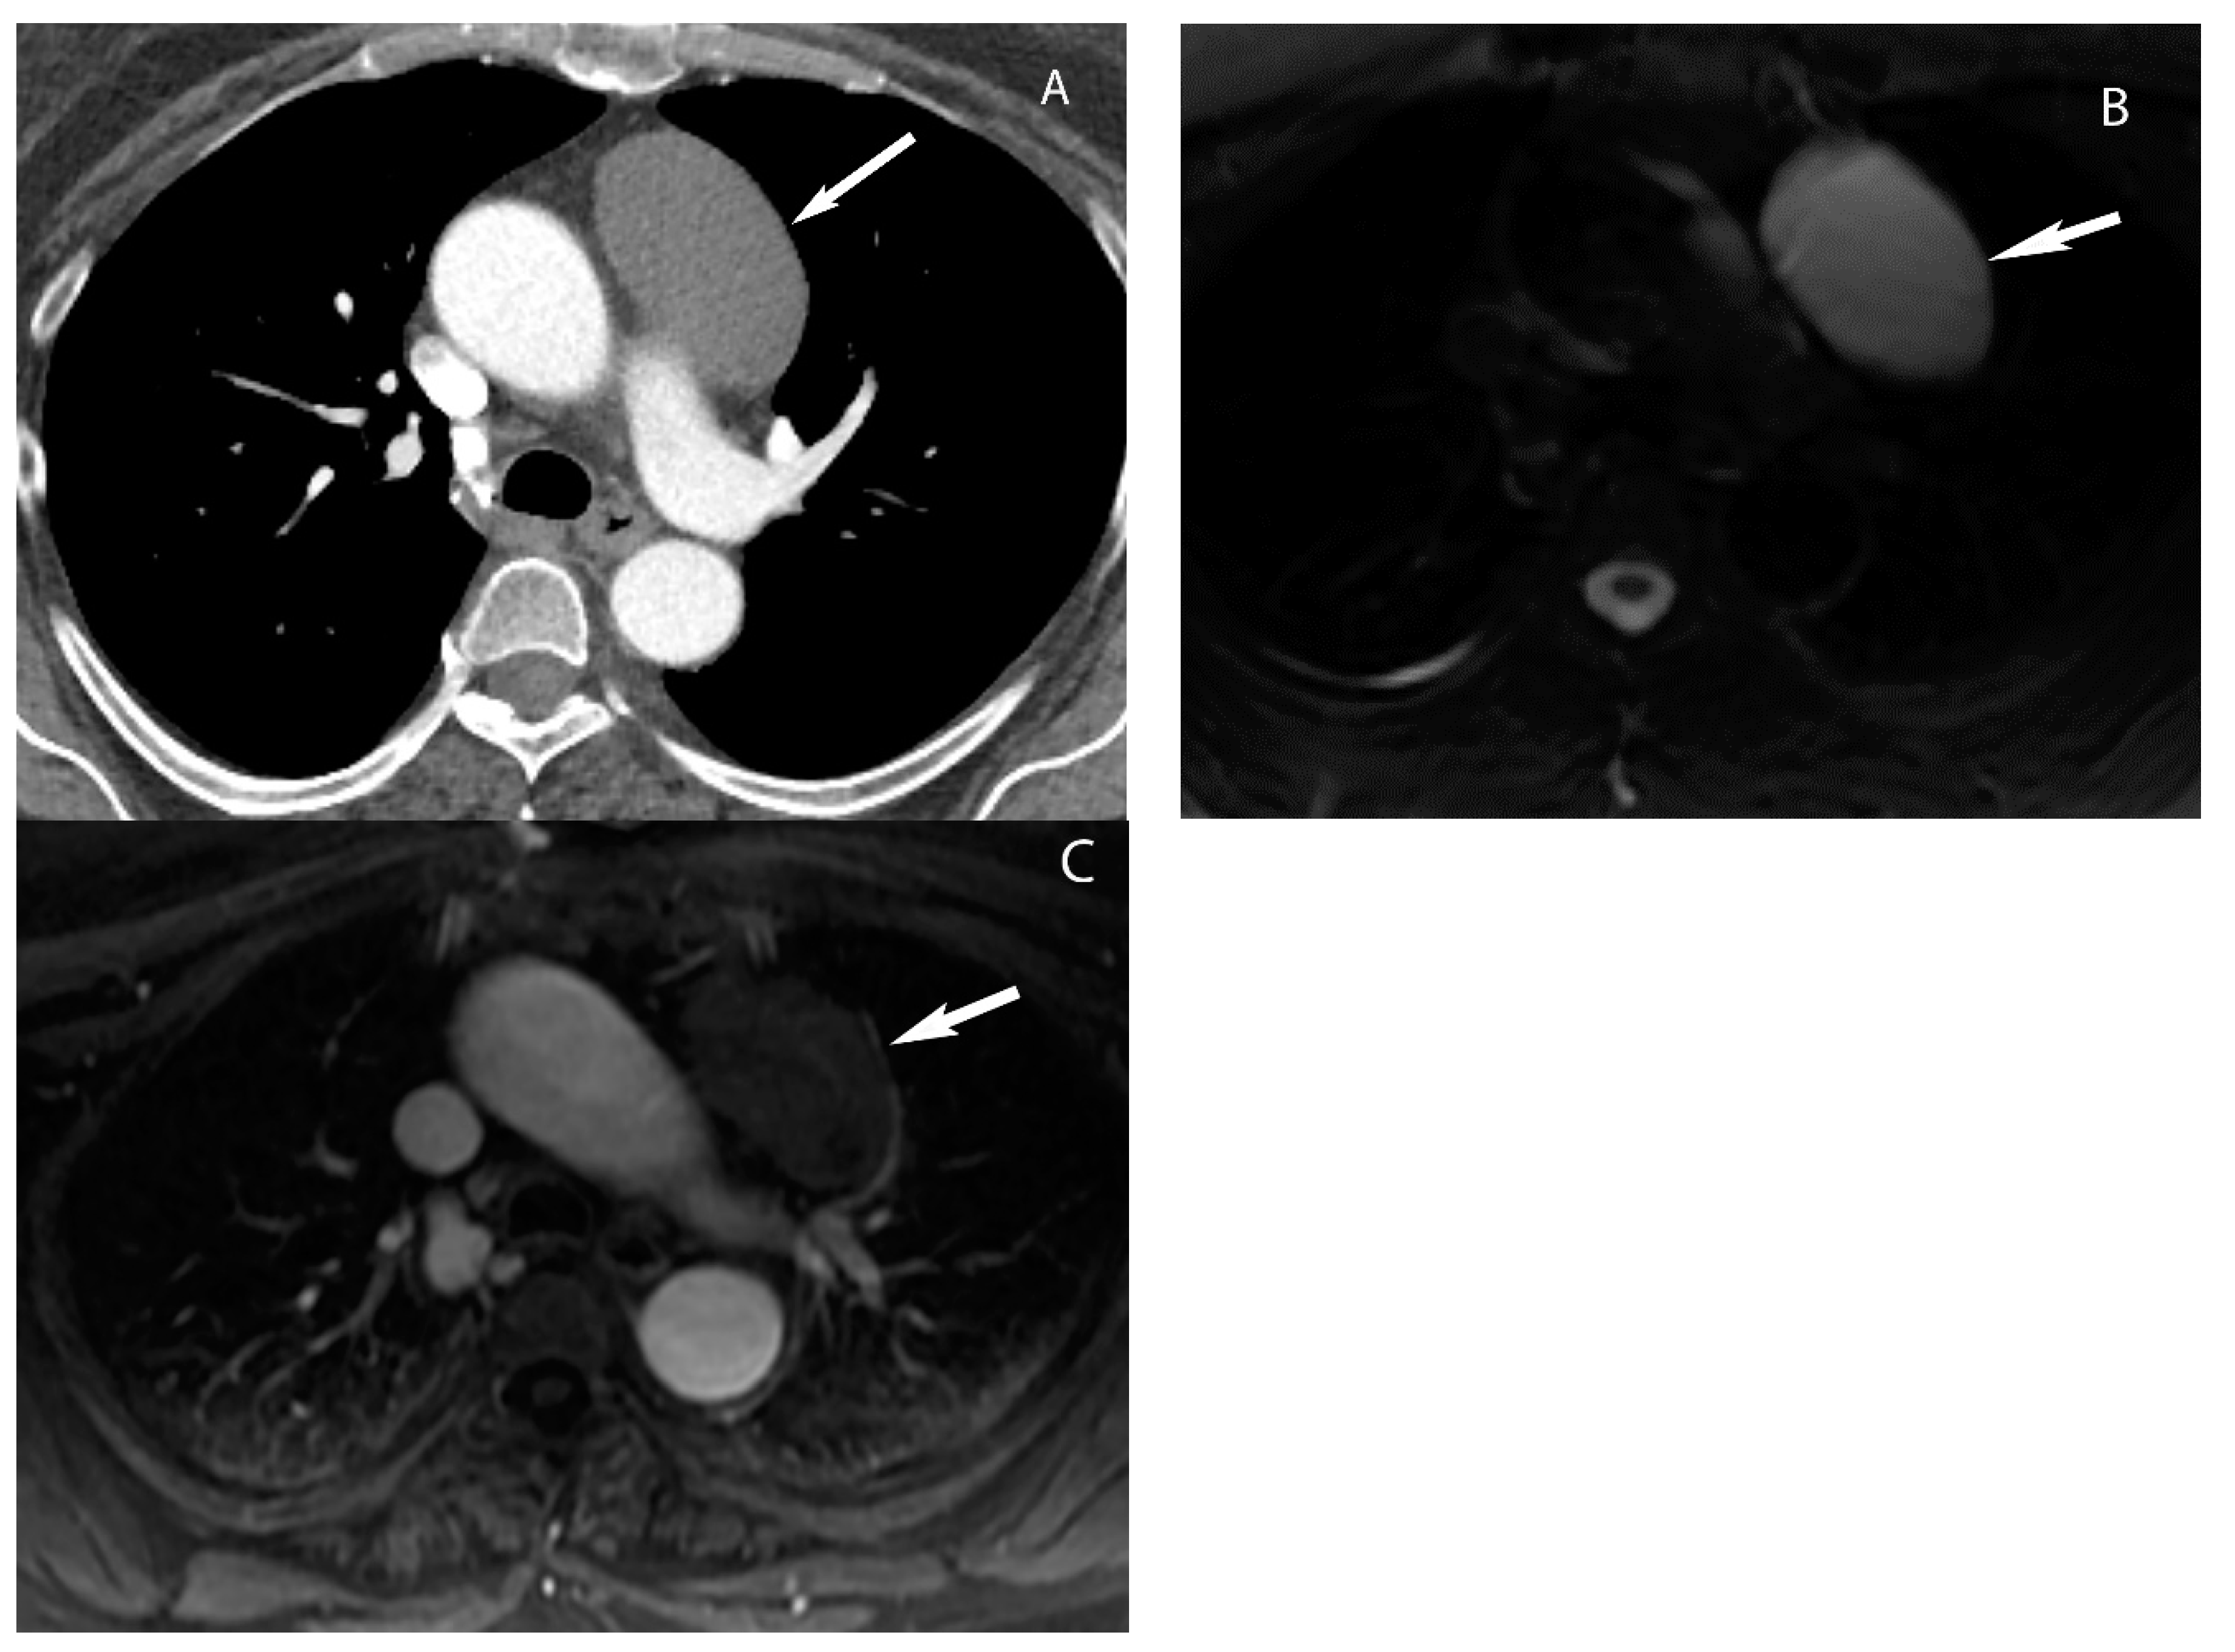

9. Hypervascular Lesions

7. Germ Cell Tumors